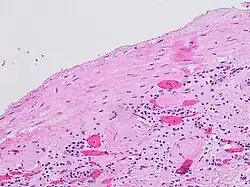

- ^ Mandolin S. Ziadie, M.D. "Simple cysts". Pathology Outlines. Topic Completed: 1 November 2011. Minor changes: 1 October 2019